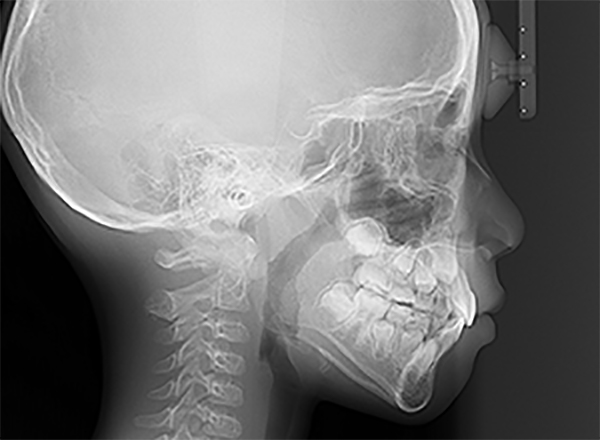

| セファロ所見 | 上下顎骨は調和のとれた位置関係を示していたが、頭蓋に対して両顎共に前方に位置していた。上下顎前歯は唇側傾斜していた。 |